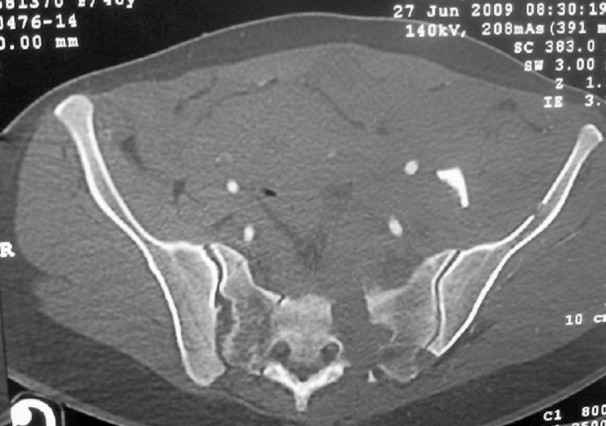

I'm posting this case on behalf of Dr. Pedro Caba, he is unable to post but able to read. 41 yo female , fall from 10 meters five days ago. Hemodynamically unstable on admission treated by angio and embolization and skeletal traction, with no external support. No associated injuries. Based on CT scan the pt has a both column fracture with conminuted dome and displaced anterior column and a sacral Denis 1 fracture with a displaced left ala. I think the best approach for the acetabular fracture is ilioinguinal with Smith-Petersen extension but don't know exactly the sequence . Will you start with the sacral fracture? Which technique? Thanks in advance Pedro Caba Unidad de Trauma Hospital 12 de Octubre Madrid Spain

This patient has extensive and complicated skeletal injuries...much more data (such as additional relevant images and clinical information regarding the soft tissues and overall patient status) would help us formulate an informed plan.

The sacral pattern alone is quite difficult and seems to be some version of an H-pattern, but I can’t tell from these films.

General condition is fine except for an intractable pelvic pain, no associated injuries (only ankle fracture), no sciatic nerve injury.

The soft tissues are also in mild condition, buttock hematoma and probably a Morel-Lavalle. I send some more CT images. There are some conminution in the posterior column (I don’t have images now). The patient is scheduled for surgery next Monday. The plan is percutaneous sacral fixation and then ilioinguinal approach .